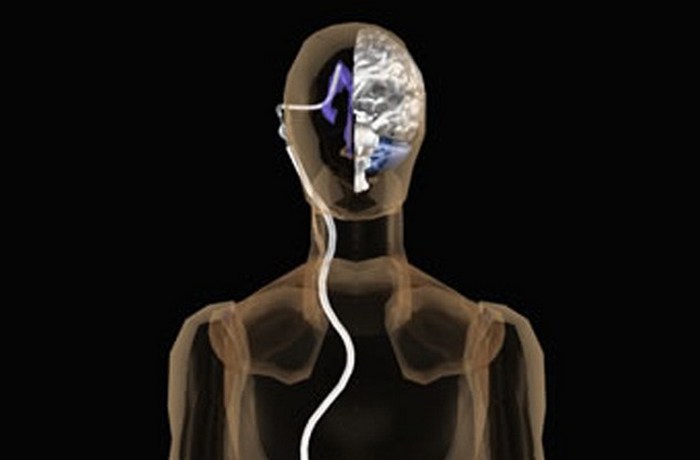

Вентрикуло-перитонеальный шунт: Показания и применение

Раздел: Фотоальбом решений